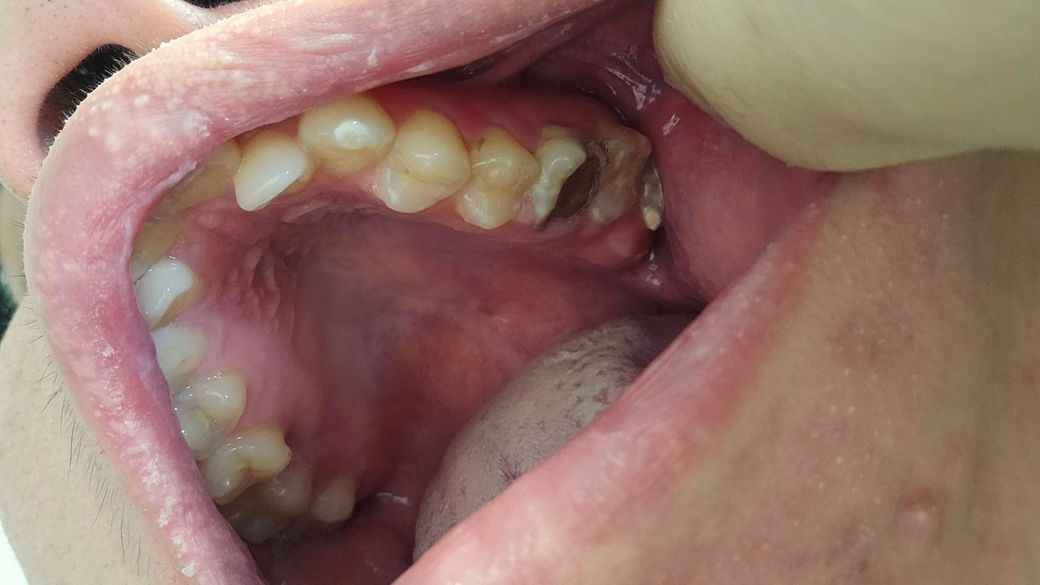

치과 갔면 무슨 치료 가능하가?아니면 발치하는가

제가 11월2일 치과 갔는데요 조금 늦게 갔는것가요? 제가 이사진찍히이빨상태 이렇게되는데요 다음주 토요일 갔도 치료할수있나요 알려주세요

치아의 상태가 안좋기 때문에 임플란트를 해야할 가능성이 높아보이고 종합적인 치료가 필요해보입니다.

사진상으로는 아래치아는 발치를 해야될것같고, 위쪽치아는 엑스레이 사진을 찍고 나서 치료 방법을 선택해야될것같습니다.

사진으로 봤을 경우에는 충치가 매우 많이 진행된 것으로 보입니다. 충치가 치아 뿌리까지 진행되었다면 치아를 발치하고 임플란트 치료 등이 필요할 수 있습니다. 자세한 확인을 위해서 치과에서 진료를 받아보는 것을 권유 드립니다.

치아 충치가 아주 깊습니다. 엑스레이 찍어보고 좀 더 검사를 해봐야겠으나 치료가 가능하다면 신경치료하고 씌우는 치료이나 발치 가능성이 높을 것 같습니다. 발치 가능합니다. 마취합니다.